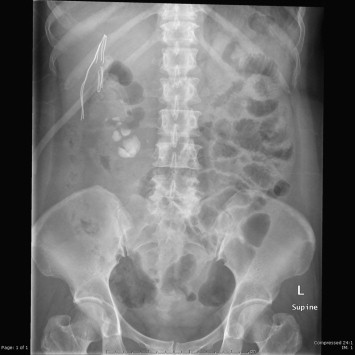

The operation was successful and a standard laparoscopic approach was not needed. The operation took 3 hours. The blood loss was 50 mL and there were no intraoperative complications. The drain was removed on the third postoperative day and the patient was discharged 4 days after surgery. After 1 month, the small residual stones (Fig. 4), measuring about 1 cm, were fragmented and cleared out using ESWL.

Small residual stone after single port nephrolithotomy.

Figure 4.